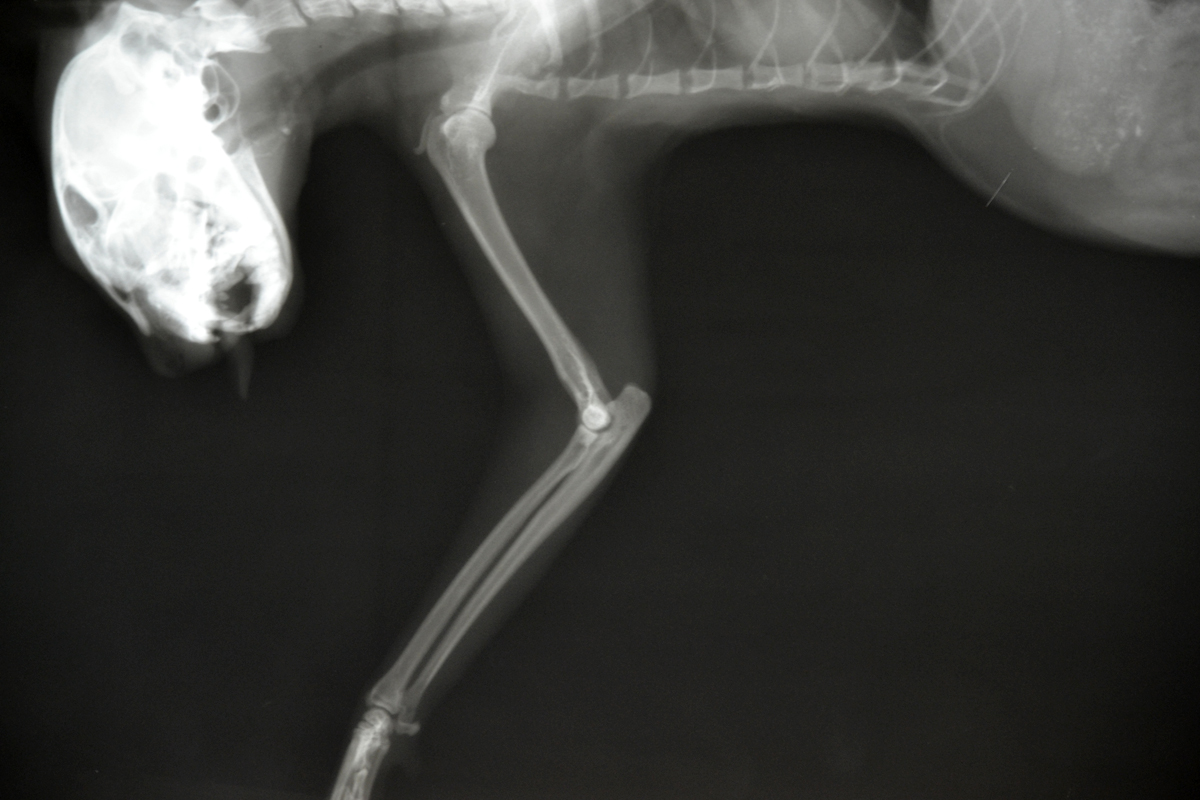

Рентген Задней Лапы Кошки: Нормы и Диагностика